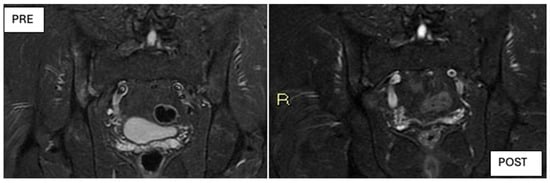

Although DISCOVER-1 and DISCOVER-2 were not originally designed to specifically evaluate axial PsA, a subsequent post hoc analysis assessed outcomes in a subgroup of patients with axial symptoms and MRI-confirmed sacroiliitis. That study reported improvements in ASDAS, BASDAI, and SPARCC MRI scores, which are consistent with the MRI findings shown in Figure 9, where notable improvements are observed following treatment with Guselkumab.

Figure 9. MRI images at baseline (t0, left) and after 6 months of treatment with Guselkumab (t6, right) showing a clear reduction in bone marrow edema and inflammatory lesions.